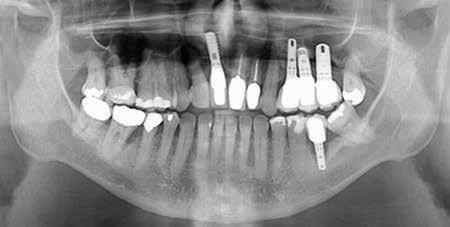

The replacement of multiple teeth with dental implants in the posterior maxilla is challenging, due to factors including low density bone and sinus morphology. When considering restoration of this region, prosthetic design will dictate implant placement. Additionally, planning must consider spacing between adjacent implants, spacing between implants and adjacent teeth and irregular alveolar ridge morphology. These key measurements translate to the final prosthesis design and will affect cleanability and future oral hygiene maintenance. These characteristics subsequently affect overall longevity of the implants and prosthesis.

This patient case report presents a complex case including an atrophic posterior maxillary region, a history of multiple failed implants, the complete lack of a sinus floor and the goal of rehabilitating normal masticatory function. Extensive grafting, 3D modeling, prosthetic splinting, and extra-maxillary anchorage were utilized in management of this case to maximize primary stability.

Case Report

A 72-year-old male presented in 2021 to the clinic with three failing implants in his upper-left-hand quadrant and desired a reliable fixed solution. The patient had a previous history of a prior failed isolated implant at site #13 in 2015. At the time, the neighboring teeth in sites #12 and #14 had a hopeless prognosis due to loss of peri-radicular bone associated with the failing implant at #13. Teeth #12 and #14 were extracted along with implant #13, and the patient received bone graft of unknown nature to the sites of #12,

#13, #14 for ridge preservation. At a later date, three implant-supported crowns in close proximity were placed in these sites. Notably, the crowns were non-splinted. (Fig. 1).

In July 2021, the patient presented with mobile implants #12, #13 and #14 to his dental practitioner (Fig. 2). The implants were removed without bone grafting.

The patient received an interim removable partial denture and presented to the oral surgery clinic for evaluation for a fixed solution. At the time of initial consultation (September 2021), it was determined that failure of the implants was due in part to excessive occlusal forces as well as lack of proper hygiene maintenance and recall by the patient. For success, prior restoration design should have minimized difficult-to-reach areas for brushing